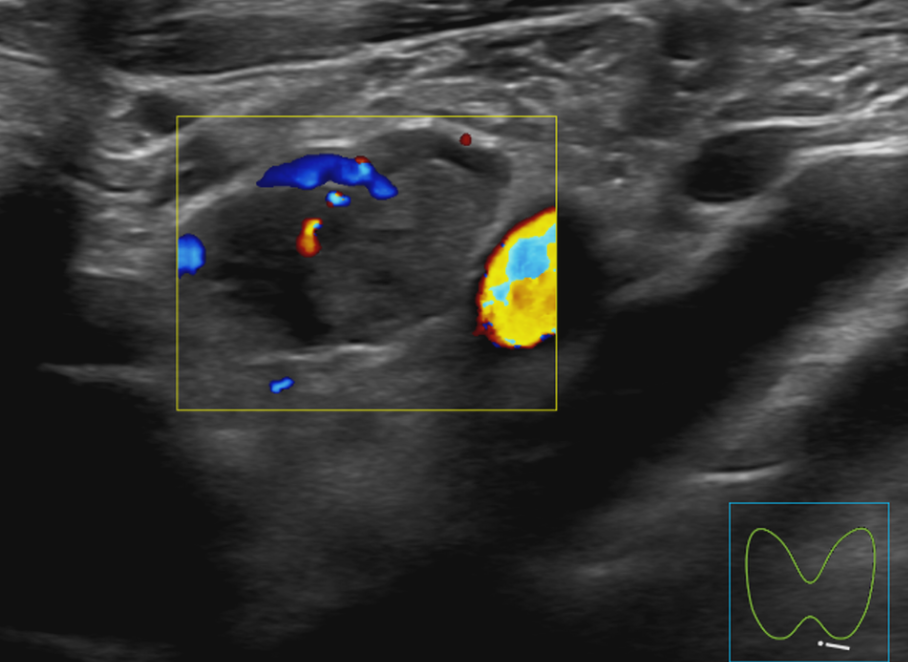

甲状旁腺结节—考虑腺瘤

术后超声造影结果显示,术前明显强化的结节已无明显强化,提示病灶灭活效果显著,治疗达到预期目标。